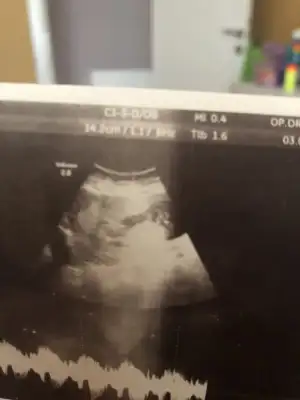

ben bugün doktora gittim geçen haftaki çıkıntıyı göremiyorum dedi.. erkek diye değerlendiriyorum demişti geçen hafta ama şimdi de karışabilir bu haftalarda anlaşılmaz falan dedi..

şaşkınlık içindeyim..

madem karışır ne diye tahmin edip fikir beyan edersin.

bu hafta usg vermedi..

geçen haftaki usg ler.. 11+2

Bence kız bu minnoş çok dik degil paralelde degil pozisyonla alakalı değilse kız diyorum

Karşıya balıyor nubu kaç haftalık usg başka varmı usg dik değil paralelde böyle usg ler beni yanıltıyor